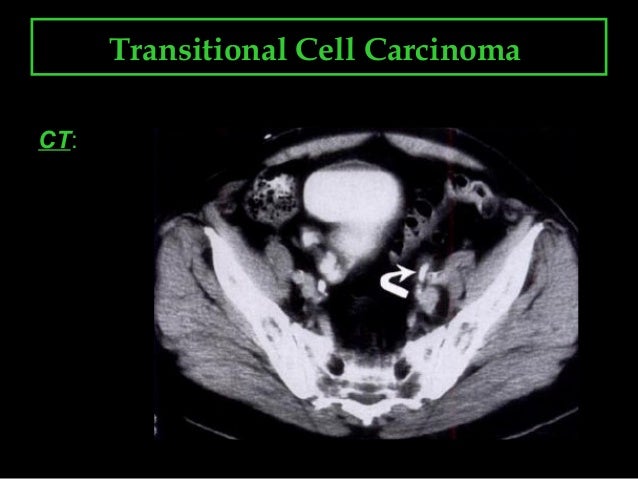

. Transitional cell carcinomas may also affect the upper respiratory tract and the ovaries. Transitional cell carcinoma (tcc) of the ureter, also called urothelial cell carcinoma (ucc) of the ureter, are uncommon compared to similar tumors elsewhere along the urinary tract but are nonetheless the most common primary tumor of the ureter.

Only your doctor can provide adequate. Although it is most common in the ovary, small series of cases in the cervix have been reported, with isolated cases described in the fallopian tube, adnexa uteri, and endometrium. Transitional cell carcinoma is one of the most common diseases found in the urinary tract or the renal pelvis area. Transitional cell carcinoma (tcc) of ovary is a rare subtype of ovarian surface epithelial tumor.